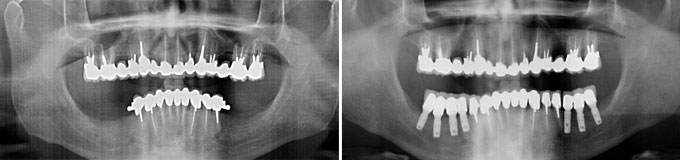

J’ai des problèmes, je refuse l’appareil mobile.

J’ai une maladie des gencives et mes dents tombent les une après les autres, je refuse un appareil que je serais obligé d’enlever

Solution : on va traiter les dents qui sont récupérables et remplacer les autres par des implants.

Implants multiples pour éviter les bridges et redonner des dents individuelles au patient avec traitement d’une maladie parodontale.

Implants multiples pour éviter les bridges et redonner des dents individuelles au patient. État final.